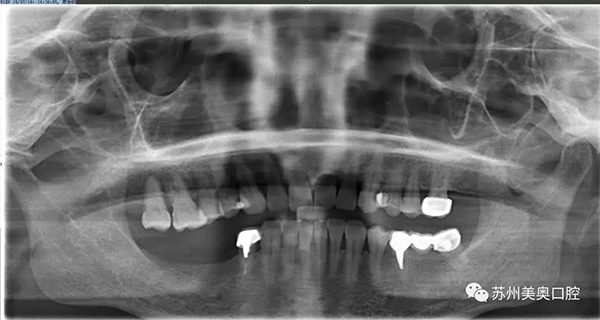

没有来到美奥口腔之前,王阿姨的牙齿情况是这样的。我们可以看到,王阿姨口内牙齿已经严重缺失,影响到了她的日常生活。